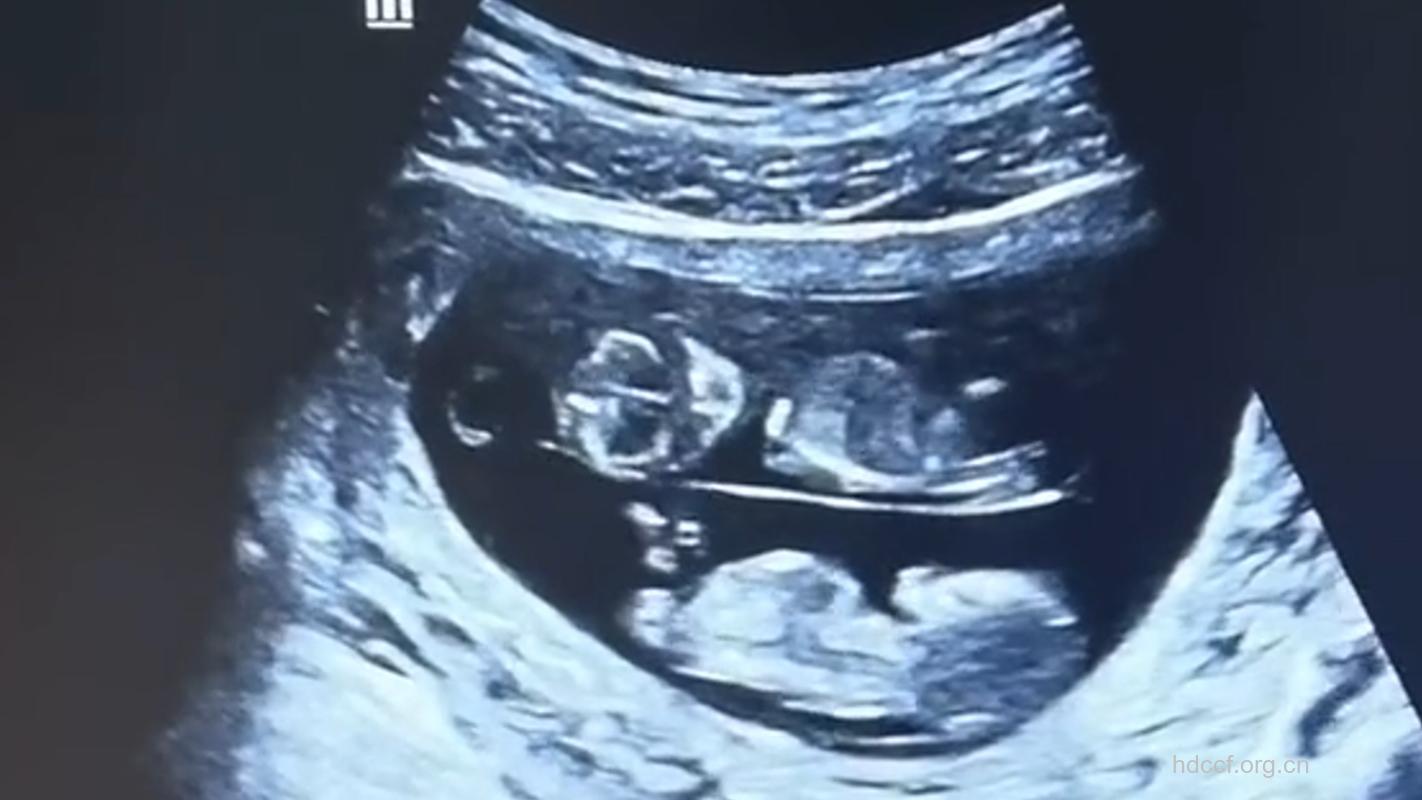

两个宝宝正忙着踢啊伸啊,他们的双手现在能在胸前相交,小小的手指甲也开始长出来了。可爱的眼皮遮着眼睛,牙床下的小牙蕾也往外冒了。